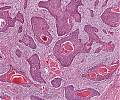

A62 Plattenepithelkarzinom (Zunge)

Gut differenzierte, epidermoide Tumorzellen mit Verhornung

-

A62 Plattenepithelkarzinom (Zunge)

Epidermoid differenzierte Tumorformationen mit Verhornung, gut differenziert

Plattenepithel_CA_Zunge1_A62.png

Invasiv wachsendes Plattenepithelkarzinom mit variabler extrazellulärer Verhornung.

Plattenepithel_CA_Zunge_A62.png

Mäßige Kernpleomorphie der Tumorzellen. Zentral Ausildung einer Hornperle.